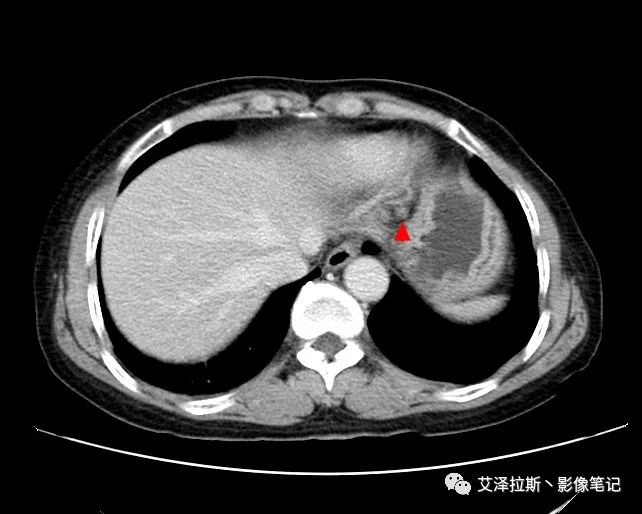

【基本情況】 患者,女性,66歲,貧血。

【影像所見】 胃竇部狹窄,胃壁環形增厚,小彎側見一巨大潰瘍,周圍伴“環堤征”,漿膜面不完整,胃周脂肪見網格狀條索影,病灶與肝臟左葉、胰腺鉤突脂肪間隙消失,增強掃描病灶明顯強化。引流區內約15個區域淋巴結受累。